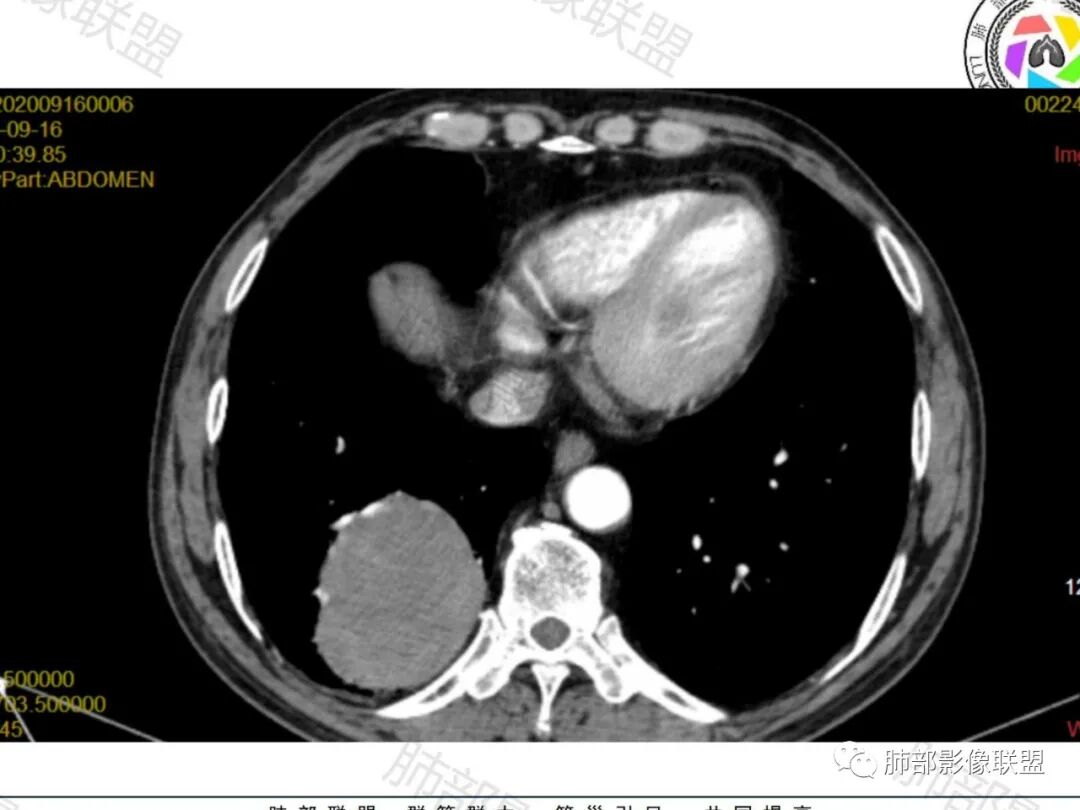

2. 血供丰富,通常增强幅度高于癌。

4. 大多有血管支气管贴边征,血管离开时比原来细一些(留下买路钱)。

肿块位于周围(起自细支气管呼吸道上皮),均匀膨胀生长(符合良性的生长特点),病灶内部大部分密度较均匀,部分小低密度不强化区(囊变),增强强化较明显,边缘血管增粗贴边,临近支气管受压,支持PSP。

但是这条血管需要交代一下:

肺动脉供血

如果这是同一根肺动脉,支持PSP

因为肺门区来源肺动脉